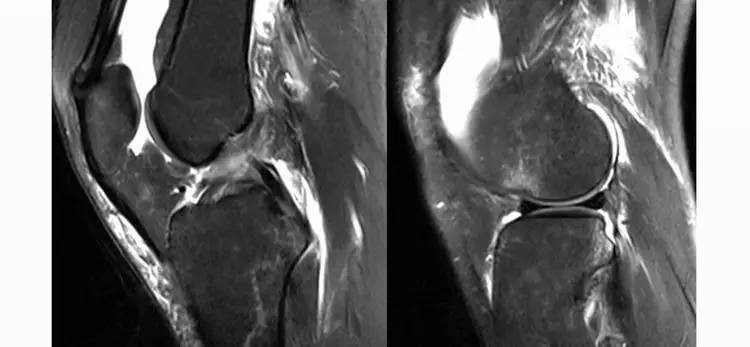

2.jpg

ACL的正常MRI表现——

1.各序列均为低信号。

2.韧带平直,边界清楚,有较好的张力。

3.韧带内可有脂肪及滑膜条纹影。